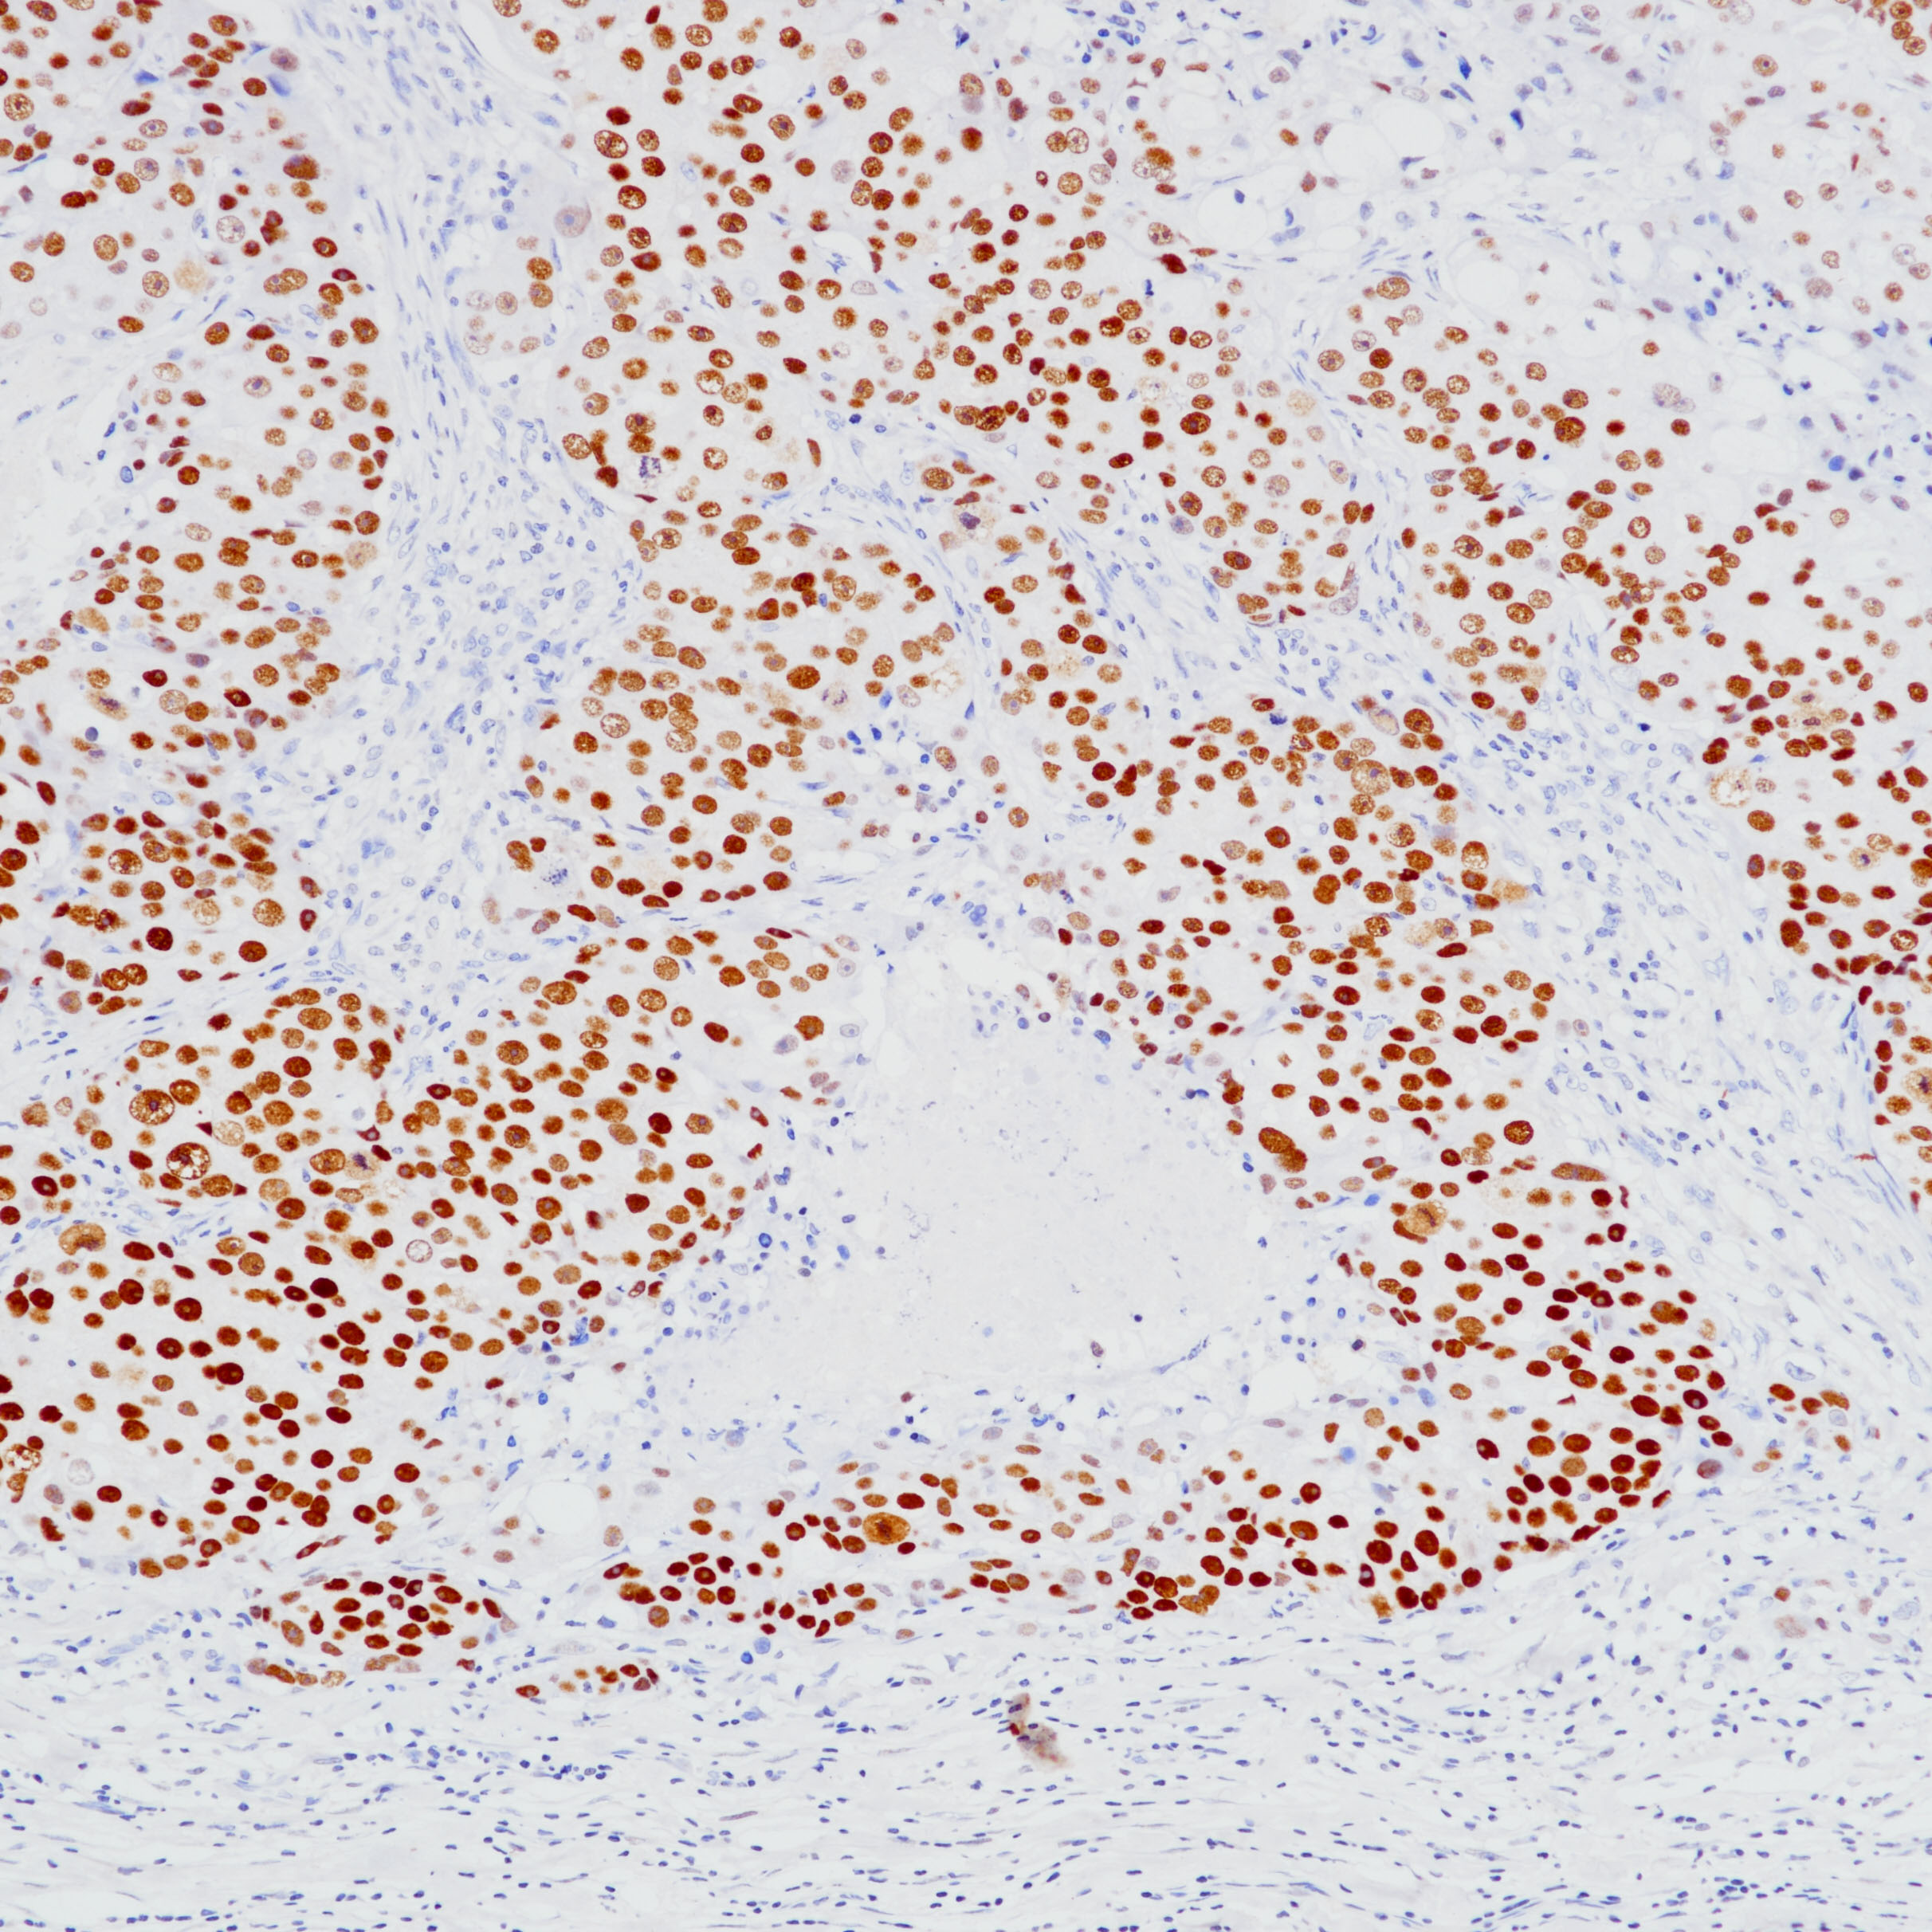

3.Parkinson B, Chen W, Shen T, Parwani AV, Li Z. TRPS1 Expression in Breast Carcinomas: Focusing on Metaplastic Breast Carcinomas. Am J Surg Pathol. 2022 Mar 1;46(3):415-423.